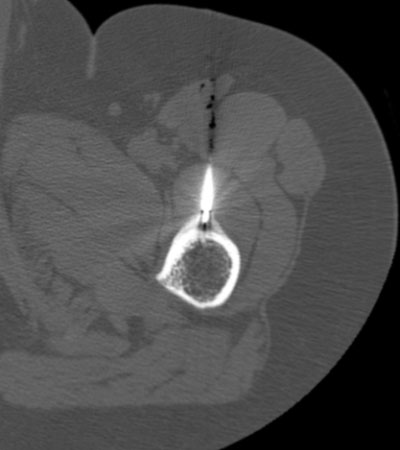

Bu yöntem hassas ve ağrılı bir işlem olduğu için görüntüleme eşliğinde (sıklıkla tomografi (özellikle osteoid osteoma uygulamalarında) nadiren floroskopi dediğimiz portabl röntgen eşliğinde) ve anestezi altında (lokal değil spinal/epidural ya da genel anestezi) uygulanmaktadır.

Elektrotun osteoid osteomada nidusa en yakın yere diğer iyi huylu tümörlerde ise tümörün merkezine yerleştirilmesi işlemin etkisi ve tedaviye yanıtı açısından son derece önemlidir. İşlem esnasında ısı kademeli olarak 90 dereceye kadar artırılıp 6-7 dakika süreyle yakma işlemi gerçekleştirildikten sonra tekrar kademeli olarak düşürülür.